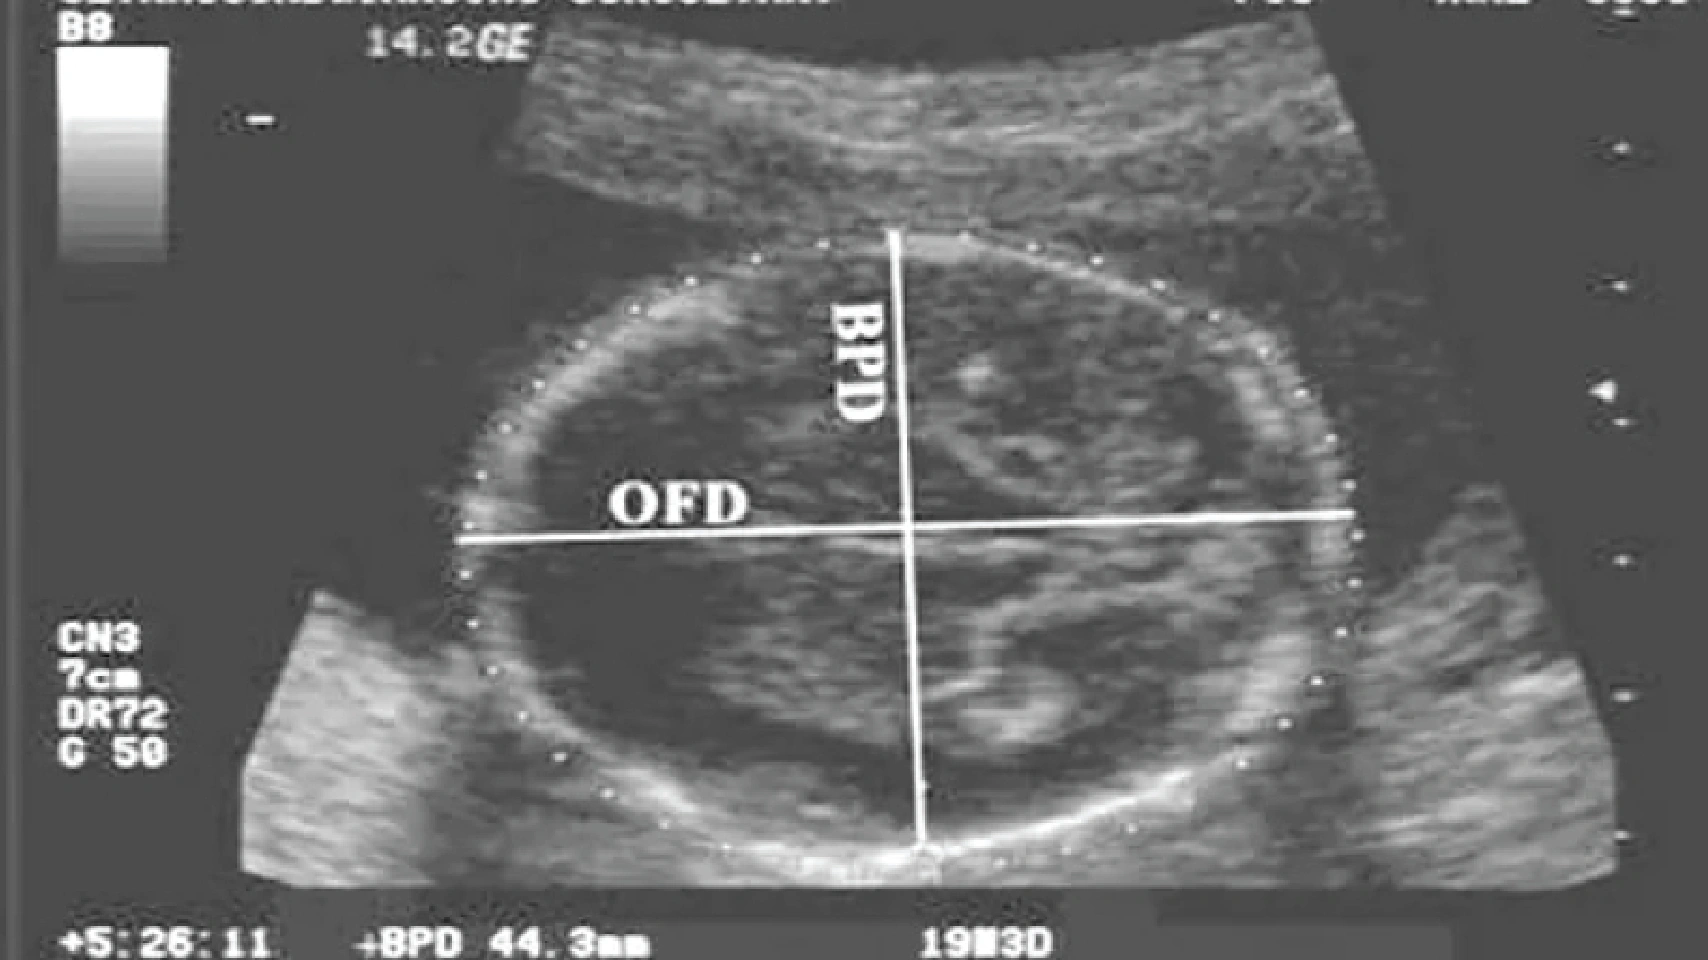

Đường kính lưỡng đỉnh (Biparietal Diameter - BPD) là đường kính mặt cắt ngang lớn nhất của hộp sọ thai nhi, được đo từ xương đỉnh bên này sang xương đỉnh đối diện.

Để dễ hình dung, mẹ hãy tưởng tượng đang nhìn đỉnh đầu của bé từ trên xuống. BPD chính là khoảng cách rộng nhất giữa hai bên thái dương của con. Phép đo này không chỉ cho biết kích thước đầu, mà còn là một chỉ dấu quan trọng phản ánh sự tăng trưởng và phát triển khỏe mạnh của não bộ thai nhi.

Trên phiếu siêu âm, mẹ sẽ thường thấy cả hai chỉ số BPD và HC (Head Circumference - Chu vi vòng đầu). Chúng mang ý nghĩa bổ trợ cho nhau để đưa ra một đánh giá toàn diện hơn.

Cách tính tuổi thai theo đường kính lưỡng đỉnh là một ứng dụng quan trọng, đặc biệt trong tam cá nguyệt thứ hai. Mặc dù các máy siêu âm hiện đại sử dụng thuật toán phức tạp, một số công thức đơn giản vẫn được dùng để tham khảo: